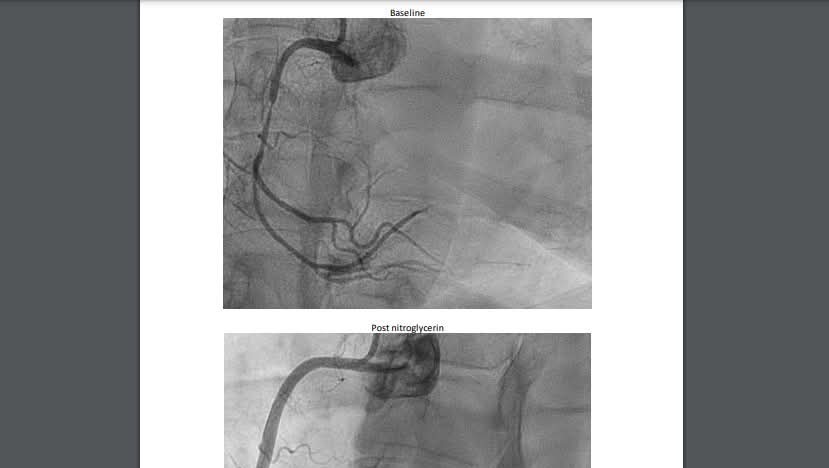

Update as of July 20: I had a second heart catherization on July 9 and had a confirmed diagnosis of Prinzmetal Angina (coronoary vasospasms). I had a 90% blockage in my right coronary artery because of a severe spasm. My symptoms have gotten worse and I can't talk or eat easily anymore. Only lying down in bed mostly helps, even then I have pain and shortness of breath.